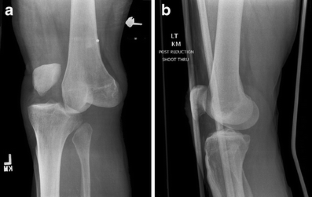

Fig. 1